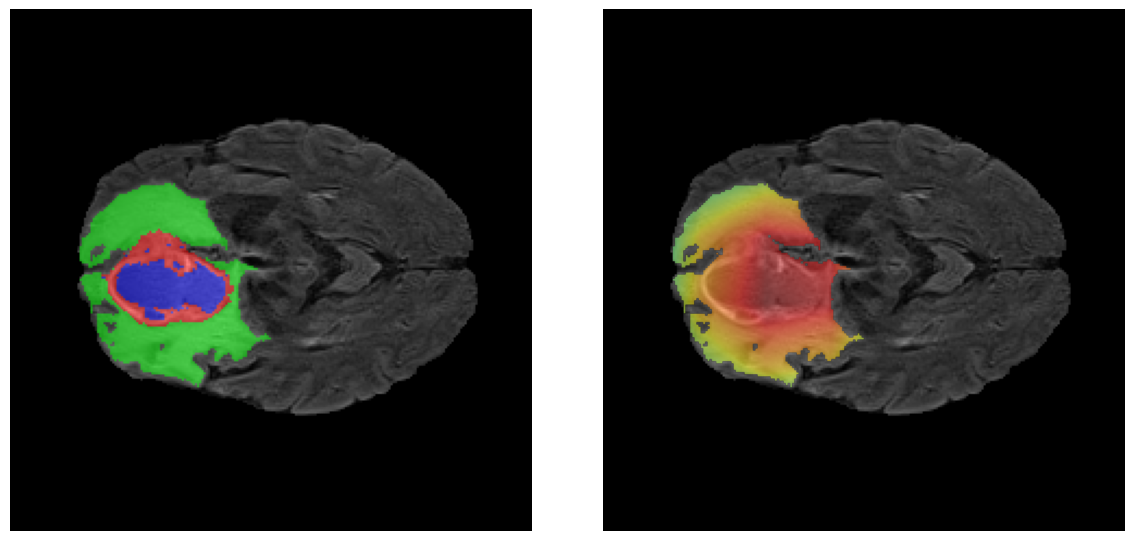

Mapas de Explicabilidad (Grad-CAM++)

Visualización de las regiones de atención del modelo que validan su razonamiento clínicamente relevante

Ejemplos HGG - Atención en Núcleo Necrótico y Tumor Realzado

HGG Grad-CAM++ 1 HGG Grad-CAM++ 2 HGG Grad-CAM++ 3 HGG Grad-CAM++ 4 HGG Grad-CAM++ 5 HGG Grad-CAM++ 6

Los heatmaps muestran que el modelo concentra su atención en las regiones de Tumor Realzado (rojo) y Núcleo Necrótico (azul), características patológicas clave de los gliomas de alto grado.

Ejemplos LGG - Atención Difusa en Edema Peritumoral

LGG Grad-CAM++ 1 LGG Grad-CAM++ 2 LGG Grad-CAM++ 3 LGG Grad-CAM++ 4 LGG Grad-CAM++ 5 LGG Grad-CAM++ 6

Para casos LGG, la atención del modelo es más difusa y se concentra principalmente en la región de Edema Peritumoral (verde), consistente con la naturaleza más infiltrativa y menos agresiva de estos tumores.

El análisis Grad-CAM++ reveló que el modelo desarrolla automáticamente la capacidad de localizar las regiones tumorales. Para casos HGG, la atención se alinea fuertemente con las regiones de Tumor Realzado (ET) y Núcleo Necrótico (NCR). En contraste, los casos LGG muestran atención más difusa, principalmente concentrada en la región de Edema Peritumoral (ED), lo cual es consistente con la patofisiología conocida de los gliomas.